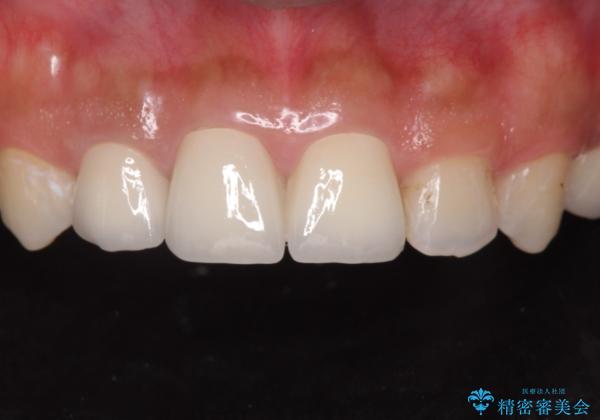

- 前歯(右上2)が黄色いとのことで来院。

レントゲンを撮ったところ前歯の被せ物が不適でした。

根管治療はご希望されなかったので(症状はなし)被せ物のやりかえ、右上2は被せ物の治療を行いました。

適合が良い被せ物が入りました。

隙間がなく被せ物が入ることによりう蝕の再発のリスクが低くなります。